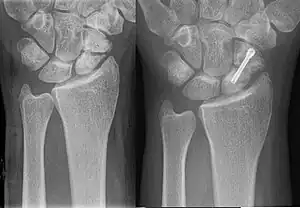

![]() | |

| An X-ray showing a fracture through the waist of the scaphoid | |